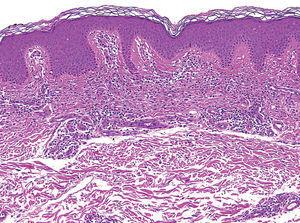

En todos los pacientes se realizaron biopsias cutáneas que mostraron hallazgos similares. Se identificaba un infiltrado intersticial en la dermis papilar y media por unas células muy monomorfas, de citoplasma redondo, con unos gránulos en su interior metacromáticos con la tinción de Giemsa (fig. 3). Estas células se identificaron como mastocitos (fig. 4).

Fig. 3.--Detalle del infiltrado de disposición liquenoide. Obsérvese la ausencia de epidermotropismo. (Hematoxilina-eosina, x40.)